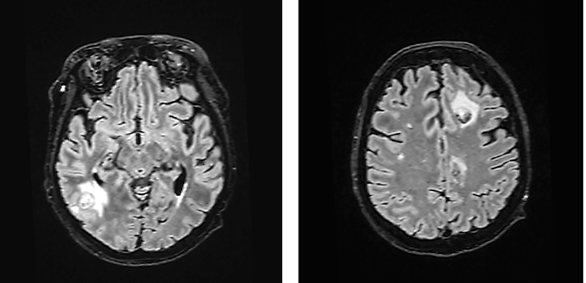

In November 2023, a 55-year-old female patient was hospitalized following a fall at home which resulted in a left elbow fracture. The patient had been feeling dizzy before the incident, prompting a head CT to exclude a head trauma and determine the cause of the dizziness. The CT revealed multiple brain lesions, with differential diagnoses including metastases and abscesses (Fig. 1), necessitating further evaluation via magnetic resonance imaging (MRI). The patient’s medical history indicates that she had been diagnosed with seropositive myasthenia gravis in July 2015. The diagnosis was confirmed by the presence of positive antibodies against acetylcholine receptors (AChR), and a muscle biopsy was performed. The patient was taking Mestinon 60mg x 3, Prednisolone 5mg x 1, and Azathioprine 50mg x 2 for treatment. Plasmapheresis was used to treat exacerbations of myasthenia gravis.

Fig. 1. Head CT scan. Multiple foci with perifocal edema in the brain – differentiate between metastases and abscesses (less likely to be abscesses)